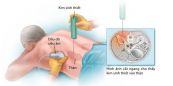

Hầu hết các mẫu sinh thiết thận được thực hiện bằng cách chèn một kim nhỏ qua da, trong thủ thuật này, thiết bị hình ảnh giúp hướng dẫn kim vào thận. Để hiểu rõ hơn về sinh thiết thận, mời các bạn tham khảo một số thông tin dưới đây.